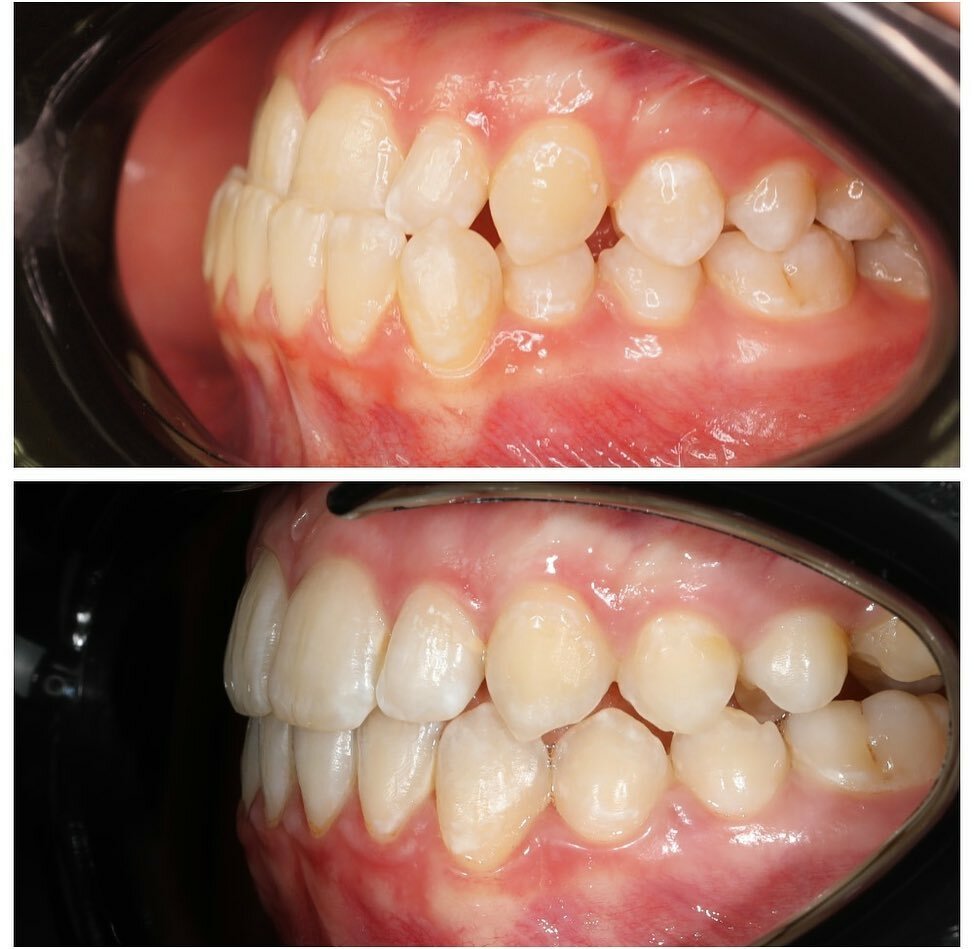

- ортодонтия

- брекеты

Gold Dent специализируется на различных направлениях стоматологии: общей терапии, хирургии, ортодонтии, эстетической и детской стоматологии, имплантологии, протезировании и эндодонтии. В клинике применяются передовые технологии, такие как цифровая стоматология CAD/CAM, лечение под микроскопом, компьютерная томография и костная пластика.